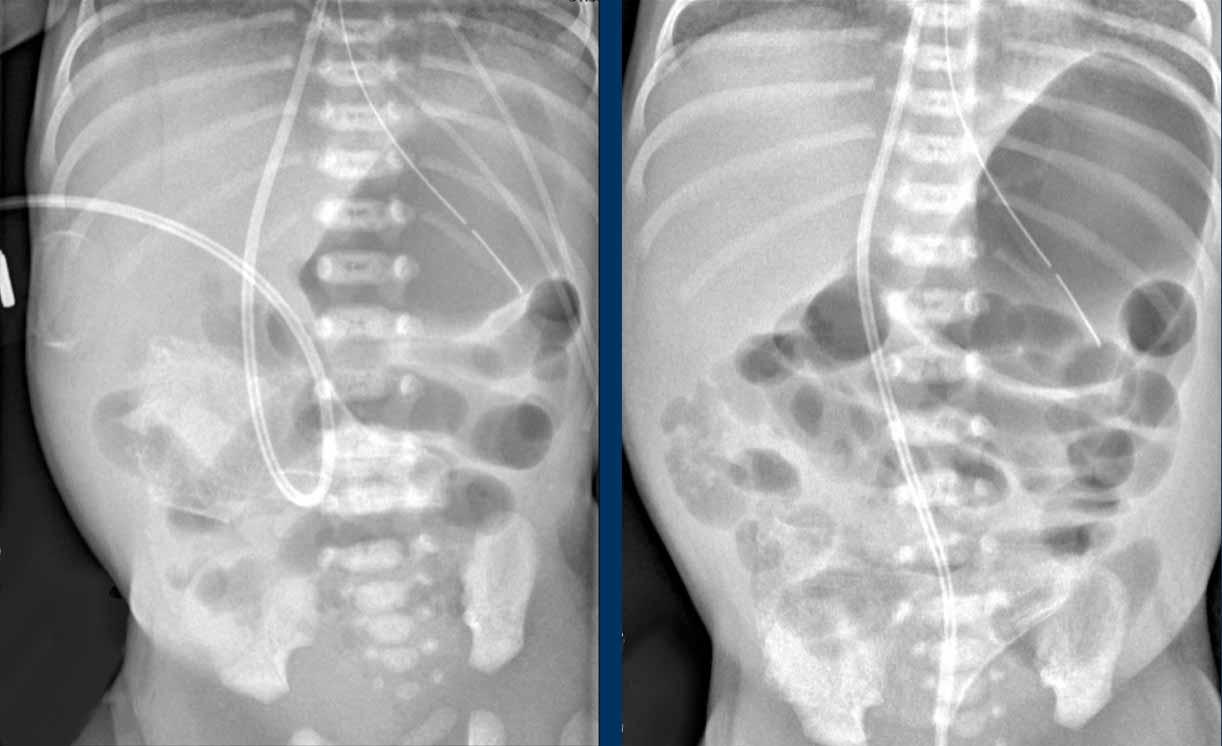

Hình ảnh

Hai phim X-quang chụp cách nhau vài giờ cho thấy ở vùng bụng trên chỉ có các quai ruột giãn nhẹ nhưng không có nếp niêm mạc, không thay đổi theo thời gian. Đây là dấu hiệu của vắng mặt nhu động ruột.

Lịch chụp lại được khuyến cáo là mỗi 6-8 giờ, nhưng tất nhiên phụ thuộc vào tình trạng lâm sàng.

Một ví dụ khác về quai ruột cố định.

Cuộn qua các hình ảnh.